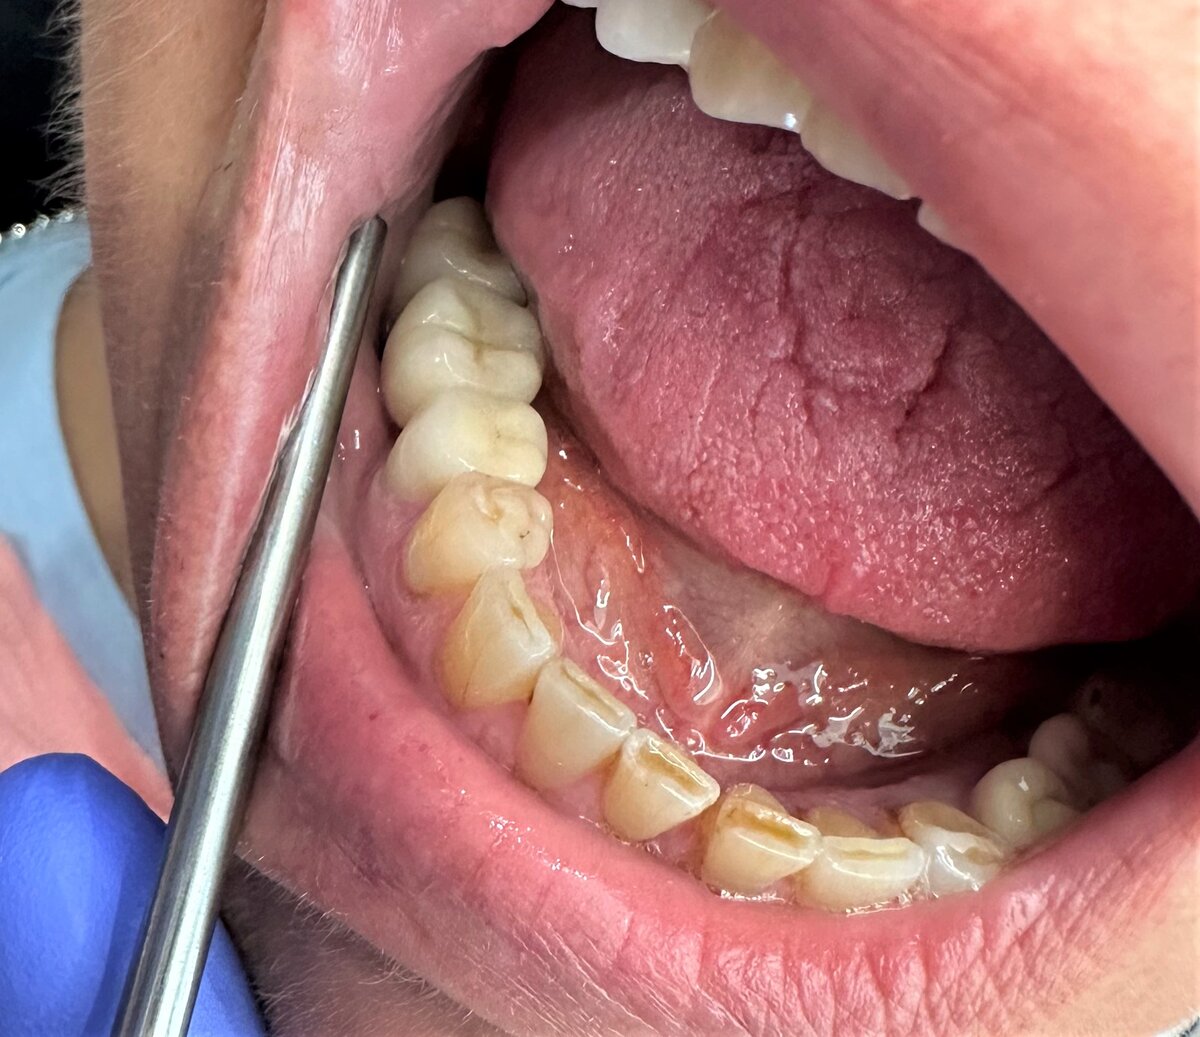

Не можем сдать мост. Вы такое можете представить? Мост из трёх единиц. Два опорных зуба и один промежуточный. Что может быть проще?

Пациентку не устраивает эта работа. Нас - тоже. Из раза в раз. И становится только хуже.

Попытка номер 1 - не нравится ширина зуба человеку, слишком широкий. Субъективные ощущения - но раз не нравится, то переделываем. Жаль, не сфотографировала прилегание. Не думала, что история затянется.

"Это вы виноваты, кривые исходники" - говорит старший техник лаборатории на букву Д (Санкт-Петербург). Ок, мало ли. Свои ошибки признавать не зазорно. Так и что в итоге? Отправили им цифровой слепок. Опять кривая работа приходит. "У вас сканер с погрешностями" - с такими?

Вам может показаться, что всё хорошо. Но смотрите дальше.

Почему техник решил оставить эти "куски"? Какой в этом смысл? Тяп-ляп.

Хорошо, ладно. Сканер, говорите, кривой. Получайте слепки аналоговые. Думаете, стало лучше? Стало совсем плохо.

Ужасно. Стало просто ужасно. Хуже, чем раньше. Курица лапой сослепу ваяла этот шедевр.

Разбор. Ну ведь очень не симпатичная конструкция. Ещё и с косяками.

Все наши замечания пропущены мимо глаз и мимо ушей. Такую работу сдать пациенту - себя не уважать.